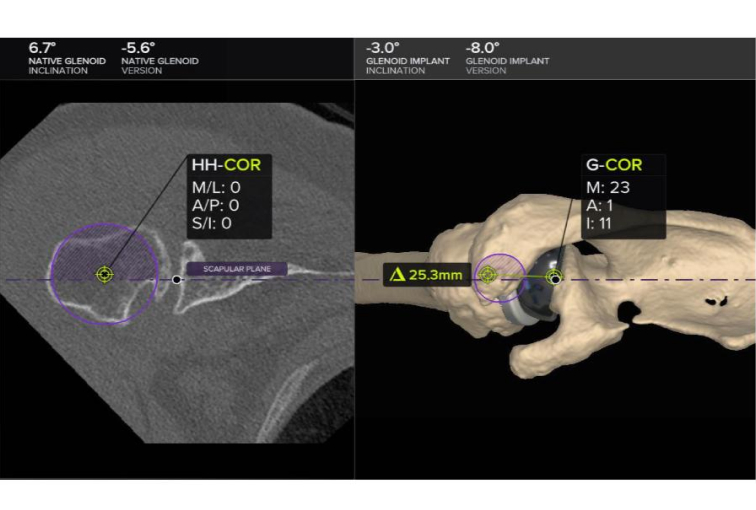

Seeking the blessings of His Holiness Jagadguru Dr. Sri Shivaratri Rajendra Mahaswami ji and offering our humble pranams to His Holiness Jagadguru Sri Shivarathri Deshikendra Mahaswami ji, JSS Hospital has achieved a historic milestone in healthcare. For the very first time in Mysuru, the Department of Orthopedics successfully performed a Reverse Total Shoulder Arthroplasty (RTSA) using state of the art Virtual Implant Positioning (VIP) technology by Arthrex.

Reverse Total Shoulder Arthroplasty is a sophisticated surgical solution designed for patients with severe shoulder dysfunction, particularly when conventional shoulder replacement proves ineffective. Individuals suffering from persistent pain, difficulty with daily activities such as combing hair or reaching the back, and pseudo-paralysis caused by rotator cuff insufficiency can benefit significantly from this approach. In this technique, the shoulder’s natural ball-and-socket orientation is reversed, where the glenoid socket becomes the humeral head and the humeral head assumes the role of the socket.

This modification empowers the deltoid muscle to compensate for damaged rotator cuff muscles, thereby restoring function and improving quality of life.